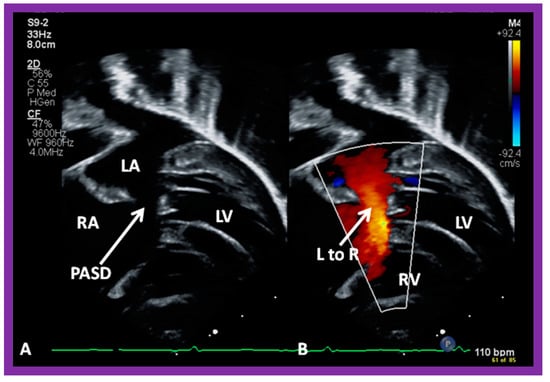

4. Patient Selection for Device Occlusion